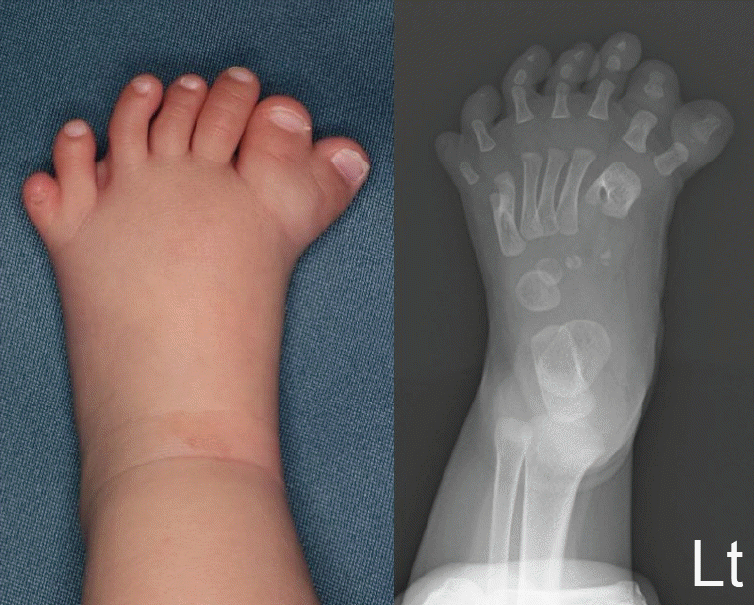

Fig. 3.

Clinical photograph and radiograph of the left foot at 9 months of age. The left foot showed both preaxial and postaxial polydactyly. The preaxial toe and the first toe had an incompletely divided metatarsal bone, with the additional toe articulating with this metatarsal bone. The postaxial toe was articulated to a metatarsal bone, with a Y-shaped configuration.

The left foot had both preaxial polysyndactyly and postaxial polydactyly (Fig. 3). The preaxial polysyndactyly bifurcated at the first metatarsophalangeal joint, with the skin component conjoined distally at the interphalangeal joint. The postaxial polydactyly bifurcated at the level of the metatarsal bone. The right foot showed postaxial polydactyly, with the additional digit branching off at the level of the metatarsal bone (Fig. 4).